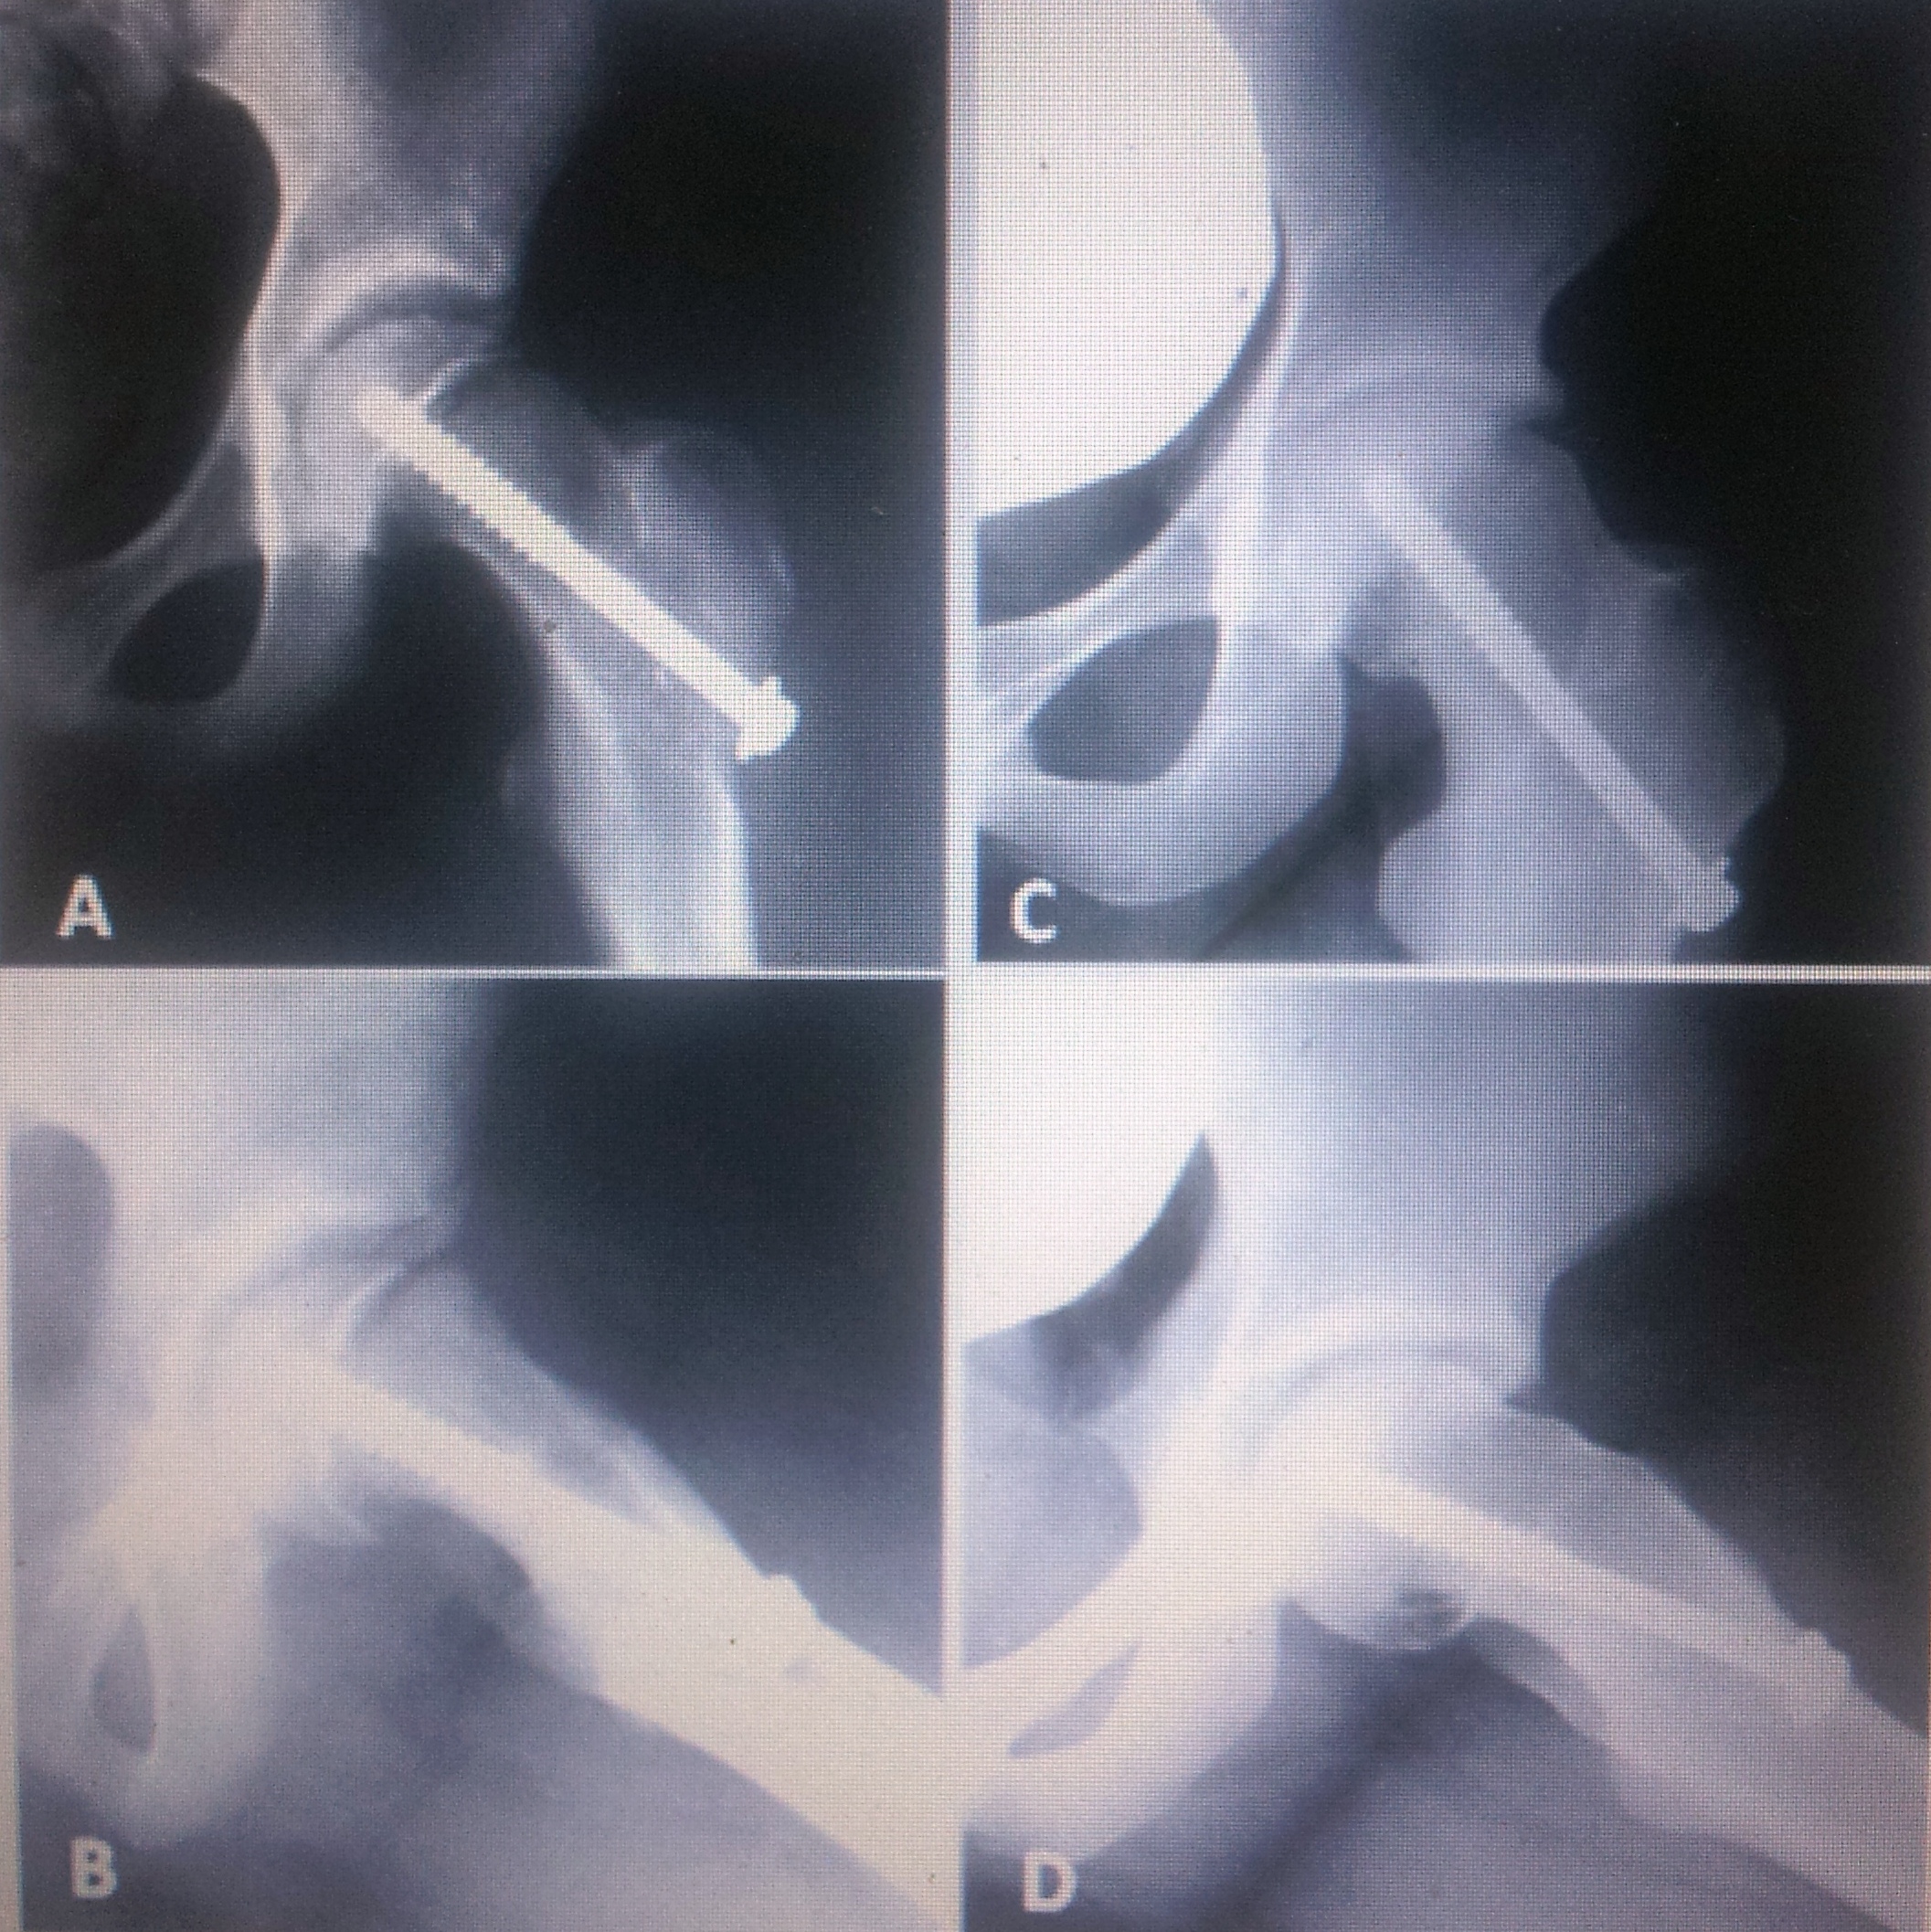

Introducción: una vez detenida la progresión del deslizamiento, las caderas experimentan un fenómeno complejo de remodelación. Mientras tanto, el choque femoro-acetabular provoca daño irreversible del cartílago articular. El propósito del trabajo es determinar si la remodelación es suficiente para impedir el deterioro articular en el corto plazo.Materiales y Métodos: se diseñó un estudio de cohorte retrospectivo de pacientes con deslizamientos moderados y graves, que recibieron como tratamiento la fijación in situ. Se evaluó la capacidad de remodelación con el ángulo de Southwick y el ángulo alfa. El deterioro funcional se evaluó con el puntaje de Harris y el radiológico, con la escala de Tonnis. Seguimiento mínimo: 4 años. Resultados: diecisiete pacientes, mediana de seguimiento: 63 meses (RI 55-81). El ángulo de Southwick prequirúrgico 57º (RI 50-72) versus el posquirúrgico 48º (RI 45-74) disminuyó significativamente (p 0,023). Lo mismo ocurrió con el ángulo alfa complementario. El deterioro radiológico evaluado con la escala de Tonnis fue estadísticamente significativo (p 0,012). Los resultados funcionales, cuantificados con el puntaje de Harris no mostraron diferencias estadísticamente significativas (p 0,49). Conclusiones: en esta serie, las epifisiólisis moderadas y graves fijadas in situ presentaron deterioro radiológico en 63 meses de seguimiento promedio. Sin embargo, la funcionalidad no se deterioró con la misma rapidez.Descargas